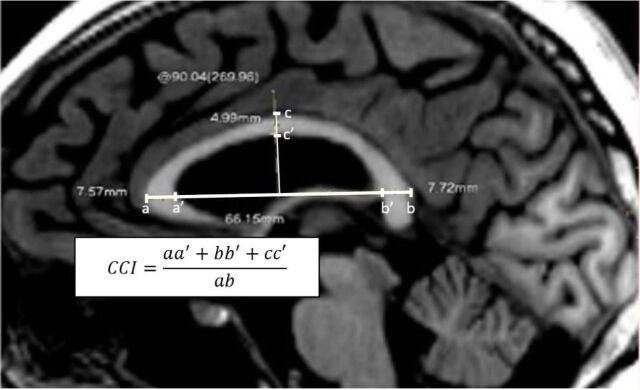

To analyze the correlation between corpus callosum index (CCI), brain volumetry, and disability in multiple sclerosis (MS) patients. The brain volumetry consists of the corpus callosum, cortical gray matter, subcortical gray matter, and white matter volumes.

This was a retrospective cross-sectional study from October 2018 to February 2019 of 30 patients with MS aged 20 to 61 years old. Brain volumetry was performed using FreeSurfer software. The CCI were measured manually using conventional best mid-sagittal T1W brain MRI. The anterior, posterior, and medium segments were measured and divided to its greatest anteroposterior diameter. Higher CCI values indicated greater corpus callosum volumes. Clinical evaluation was comprised of MS subtype, age of onset, relapse frequency and Expanded Disability Status Scale (EDSS).

Thirty MS patients with median of age 22 years were included. Relapsing-remitting (RRMS) subtype were 73.3%. Very significant correlations were shown between the CCI and corpus callosum volume (CCV) (r=0.79; p<0.0001) and cerebral white matter volume (r=0.81; p<0.0001). Significant correlations were shown between the CCI and cortical gray matter volume (r=0.64; p<0.0001) and subcortical gray matter volume (r=0.69; p<0.0001). The CCI was positively correlated with age of onset and inversely with EDSS. The CCV and CCI were smaller in secondary progressive MS (SPMS).

The CCI is easy and fast to obtain in conventional MRI and significantly correlated with brain volumetry, age of onset and disability in MS patients.